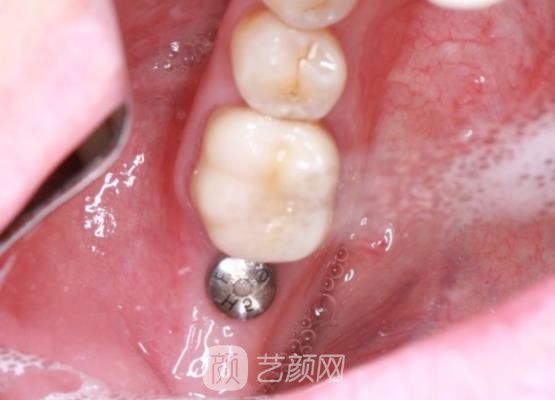

整个手术在调节的过程中其实都是比较轻松的,也没有用了多久的时间,大概用了有两个小时左右的时间吧,在完成手术之后医生告诉我很多关于手术之后应该注意的是想让我回家以后遇到什么不懂的都要去问,这样才能让手术更好的恢复。

后期了解了情况之后我就回家了,回家之后我一直都很配合医生,而且我也会按照医生的安排时间去医院做复查,所以感觉用了四五个月的时间,我的牙齿调节部位就恢复了,现在的牙齿重新又长回来了,而且用手摸了一下,一点都没有那种冲动的感觉,哈哈,我好开心呀。